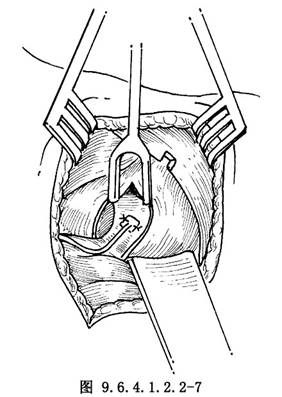

9.5 5.將神經肌蒂固定於環杓後肌

將已製備好的神經肌蒂置於環杓後肌肌腹部表面,以5-0尼龍線固定2~3針(圖9.6.4.1.2.2-7)。多采用雙肌蒂法。